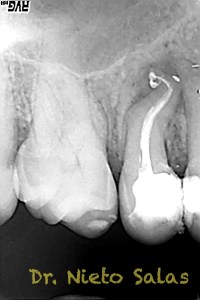

Y  de forma muy similar en el caso B; en este caso el paciente vino a la revisión a los 9 meses evidenciado el éxito en el tratamiento:

Con respecto a lo puramente endodóntico, la verdad que fueron unos casos de verdadero estrés para no perder la permeabilidad ni la long de trabajo, con técnica corona-apice y con un diametro apical de 20, instrumentado solo la parte apical con limas de Mtwo , la parte coronal me ayudé de ultrasonidos. No sé, que más contarte con respecto a la conformación de los conductos.